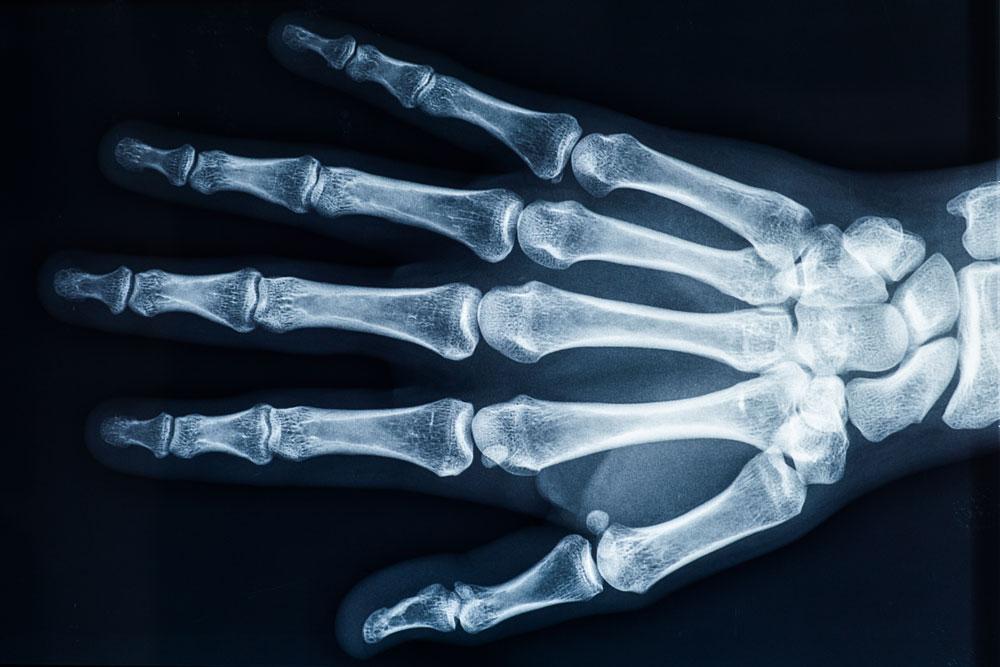

The Welsh Government is investing £1.3 million to upgrade x-ray facilities in Morriston Hospital’s emergency department in Swansea.

A 15-year-old system will be replaced with modern digital technology that produces instant high-quality images, leading to quicker results.